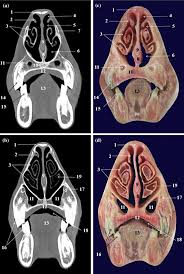

Nasal Cavity Cadaver Labeled - Nose Nasal Cavity - Scott brown, md duke university medical center.. Carlson respiratory system overview (labeled), illustration ss21310679. In addition to being an integral part of the respiratory system, your nose also serves as the organ of olfaction or smell. Read the labels on all the. Abi hachem engages the ent residents at duke university hospital, instructing them on how to dissect the nasal cavity to expose the frontal sinus, and identifying relevant anatomy. Nasal cavity and paranasal sinuses.

Each image highlights and labels the sinuses in coronal and sagittal view. The nasal septum divides the cavity into two cavities, also known as fossae. The nasal cavity forms part of the aerodigestive tract. The nasal cavity is divided in two by a vertical fin called the nasal septum. The nasal septum divides the nasal cavity into two chambers.

The nasal septum divides the cavity into two cavities, also known as fossae. Nasal cavity and sinus tumors are usually treated with surgery. Carlson nasal, oral & laryngeal cavities, illustration ss21310241. Explore over 200 cadaveric images right at your fingers, providing a new supplemental interactive experience for dissection labs. In front of the face, the nasal cavity opens with nostrils, behind it through the choana, it communicates with the nasopharynx. The nasal cavity forms part of the aerodigestive tract. The cavity of the nose (cavum nasi) is divided by the septum of the nose into the right and left halves. In addition to being an integral part of the respiratory system, your nose also serves as the organ of olfaction or smell. The nasal cavity (or nasal fossa) is a large air filled space above and behind the nose in the middle of the face. Radiology axial cadaver images nasal cavity dissection video. Inferior, middle and superior nasal conchae (turbinates) superiorly: Nasal cavity definition, anatomy, functions, diagrams. The nasal septum divides the nasal cavity into two chambers.

Inferior, middle and superior nasal conchae (turbinates) superiorly: nasal cavity labeled. Each image highlights and labels the sinuses in coronal and sagittal view.